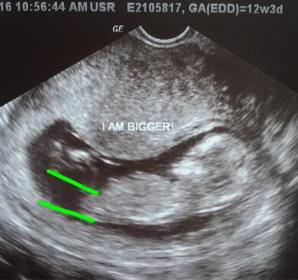

Or is is the 2 white lines in the first image? I appreciate everyone's help. I'm driving myself crazy :)

Thank you!!! Is it the angle that is making you guys think boy? Attachment 31462

The two things that I see are these. First pic, a pretty good angle on the nub, and the last pic looks like it may have a bump on the end which makes me think boy. Certainly not 100% on my guess by any stretch, could be a girl for sure but it's my beat guess.